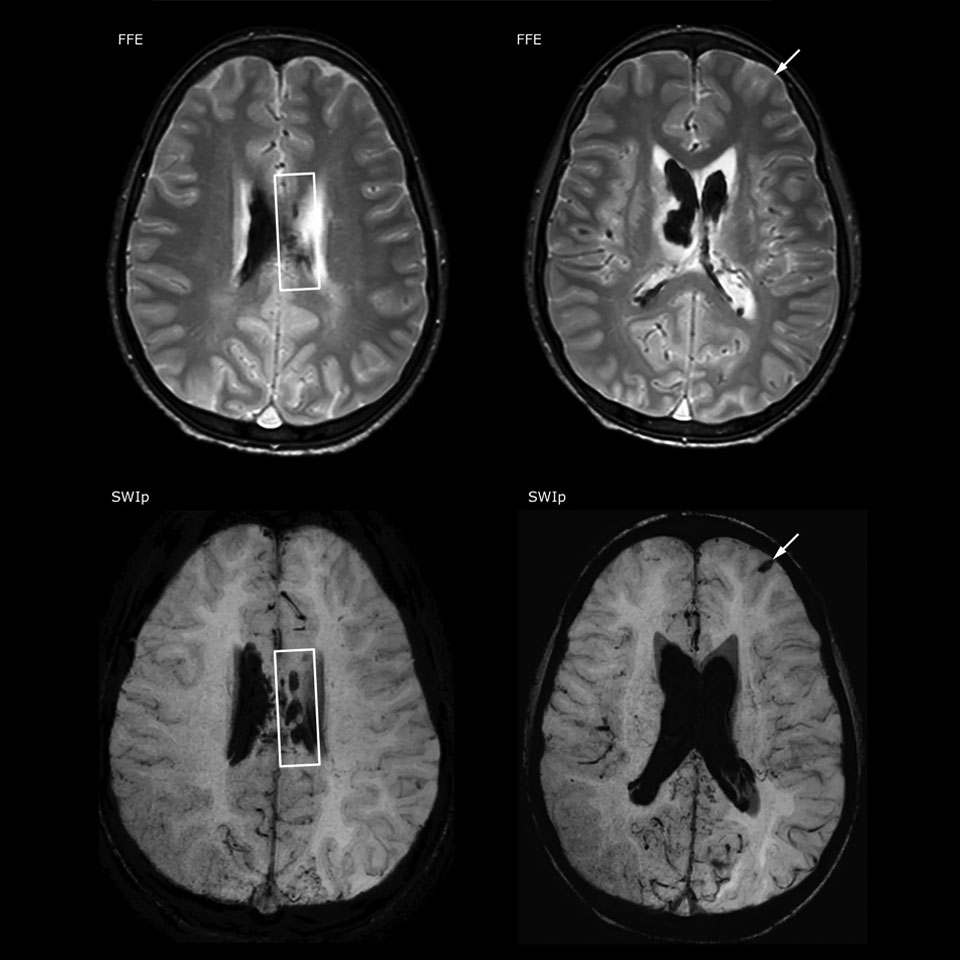

La valeur de l’imagerie de susceptibilité pondérée dans la visualisation des lésions cérébrales est bien documentée. La technique SWIp multi-écho de Philips offre une imagerie de susceptibilité pondérée rapide avec un contraste de susceptibilité amélioré et une haute résolution.

“La SWIp nous aide à identifier le sang ou les produits sanguins, la calcification et les maladies qui touchent le système vasculaire”, indique le Dr Miller. “Chez les enfants atteints de traumatisme crânien, elle met en évidence les zones affectées mieux que certaines des techniques que nous utilisions auparavant. Ces enfants présentent souvent des micro-lésions qui endommagent légèrement le sang et les tissus. L’utilisation de la SWIp nous aide à mieux caractériser l’étendue et la nature de la lésion. La caractérisation optimale d’une lésion favorise la fiabilité du diagnostic.”

“Je recommande vraiment aux autres utilisateurs d’adopter la SWIp. À l’origine, nous avions ajouté la séquence SWIp après nous être renseignés sur son utilité dans la littérature. Ensuite, nous avons directement comparé la SWIp aux séquences 2D à écho de gradient que nous utilisions. Après de nombreuses expériences cliniques pour en observer les avantages, nous étions assez confiants pour remplacer les anciennes séquences par des SWIp. Cela nous apporte une meilleure évaluation des processus physiologiques du cerveau qui étaient moins visibles sur nos anciennes séquences d’imagerie”, déclare le Dr Miller. “La SWIp est désormais notre séquence de base pour examiner les patients victimes de traumatismes crâniens au PCH, et nous l’utilisons épisodiquement pour les patients atteints d’anomalies vasculaires intracrâniennes.”

“Je crois que la SWIp est rapidement en train de devenir la norme dans l’imagerie des traumatismes crâniens grâce à sa haute sensibilité aux produits sanguins veineux. La SWIp peut même aider à attirer les patients ; nos neurochirurgiens nous demandent souvent d’examiner leurs patients sur nos scanners avec des techniques hautement sensibles comme la SWIp. On constate également une application grandissante des séquences SWIp sur d’autres anomalies vasculaires grâce aux possibilités d’évaluation physiologique du cerveau, par rapport à une imagerie structurelle standard.”